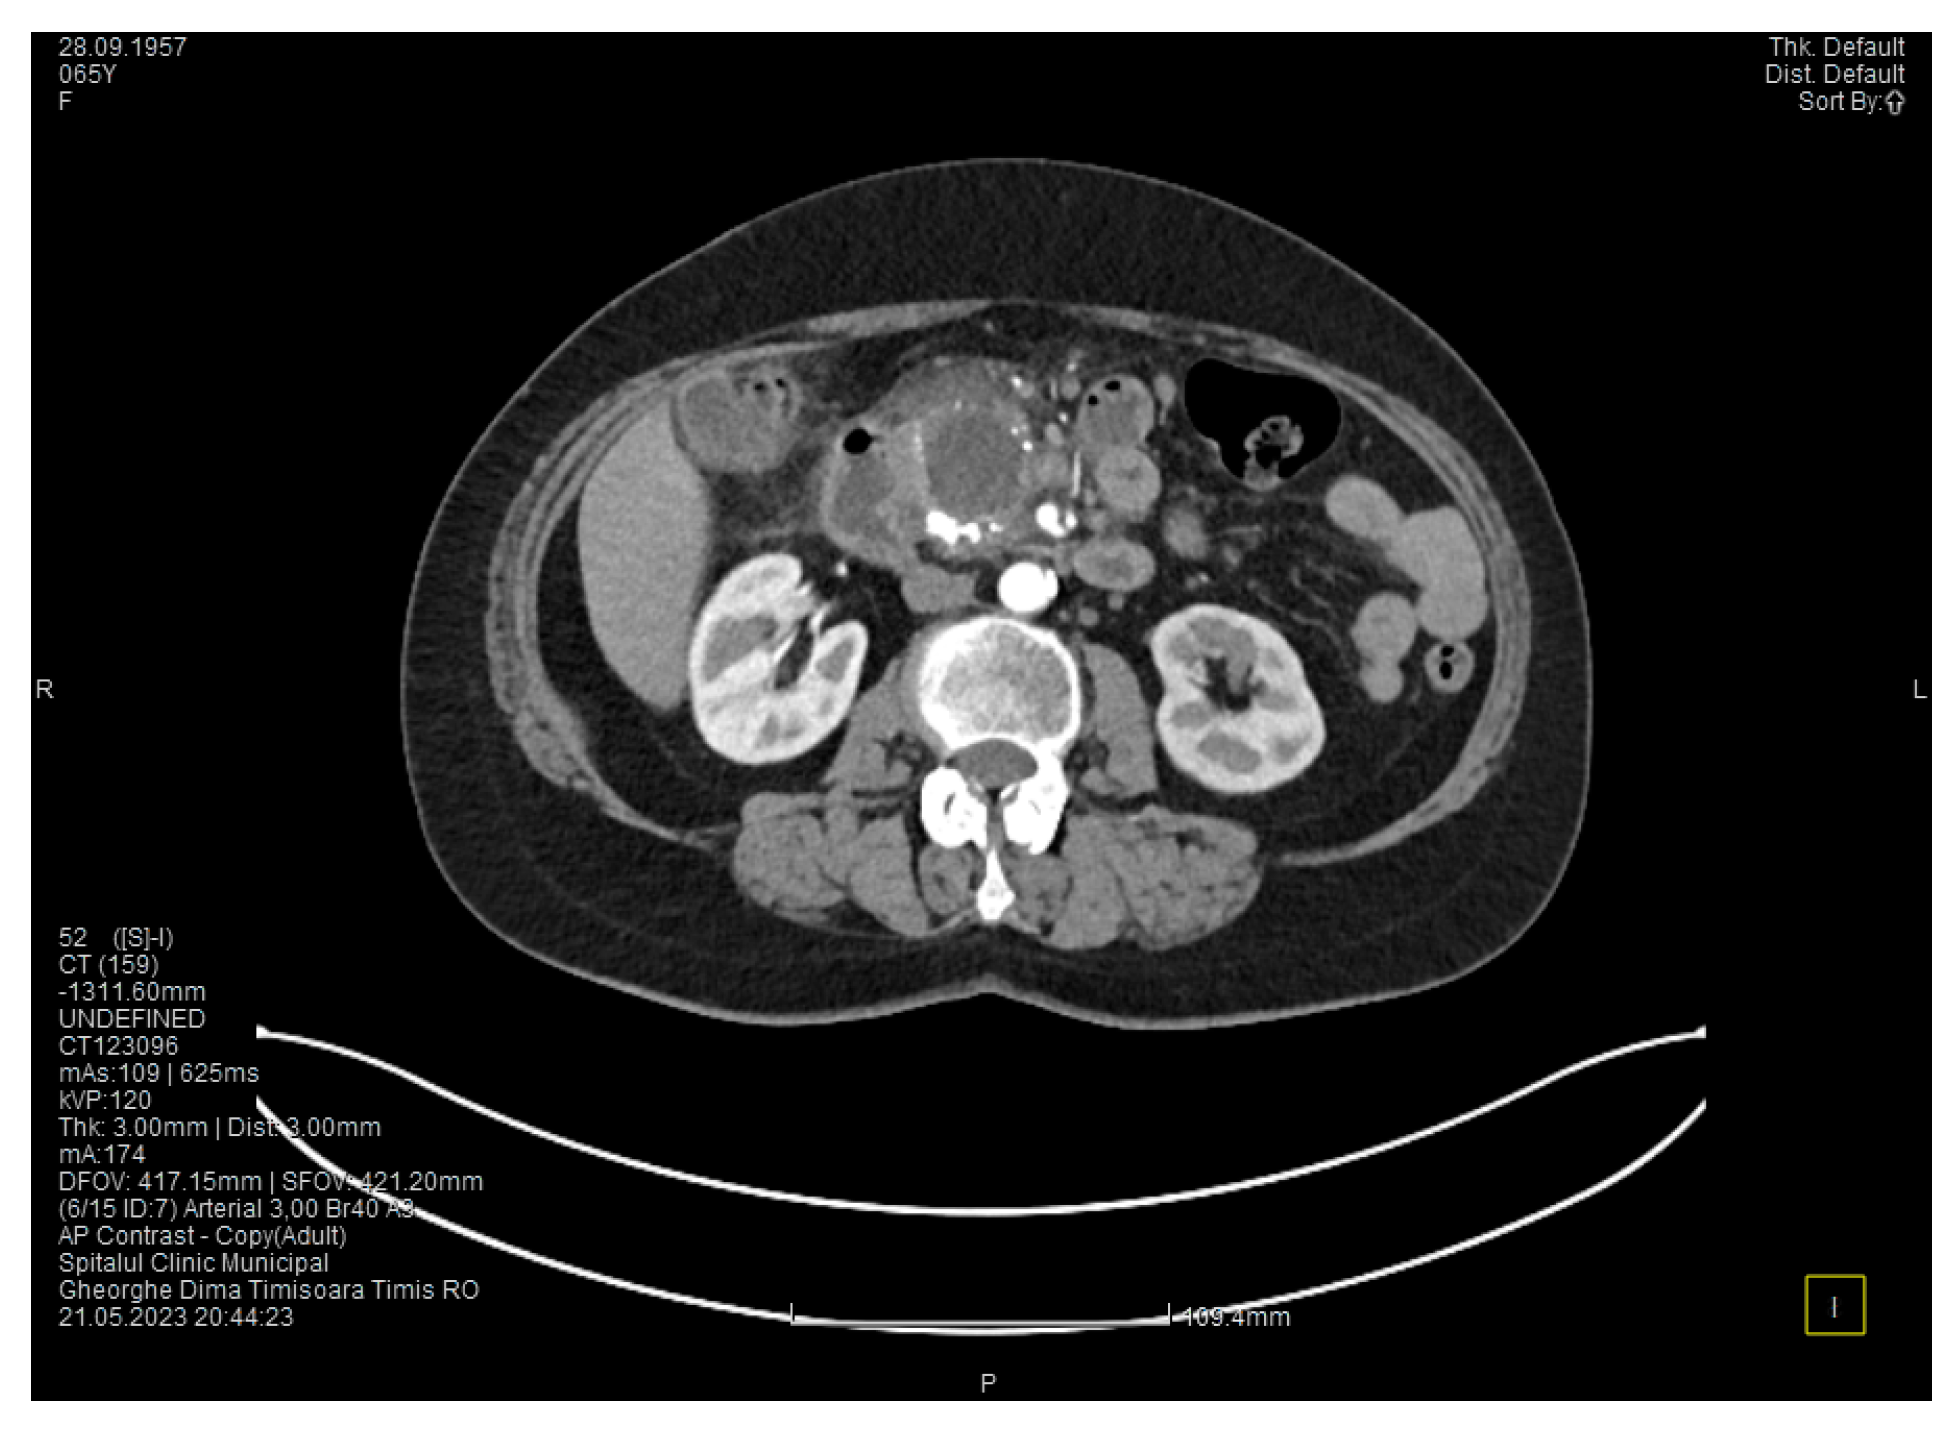

Contrast-enhanced computed tomography highlighted signs of chronic pancreatitis with multiple calcifications throughout the pancreatic parenchyma, calcareous conglomerates in the cephalic area (Figure 5), dilatation of the Wirsung duct measuring approximately 15 mm, a cephalo-uncinate pseudocyst measuring 30/31/32 mm (Figure 6), and densification of the pericephalic pancreatic fat; all the changes were more pronounced compared to the previous examinations. Other findings included acute cholecystitis with thickening of the gallbladder wall and iodophilia of the mucosa, small dilatations of the intrahepatic bile ducts, fluid accumulation in the hepatic hilum and in the periduodenal area, inflammatory wall thickening in the gastric antro-pyloric region and in the duodenum (I, II), and inflammatory lymph nodes in the peripancreatic area and in the hepatic hilum measuring up to 11 mm.

Figure 5. CT scan at the fourth episode of acute pancreatitis shows calcifications in the pancreatic head, thickening of the duodenal wall, and partial occlusion of the duodenum.